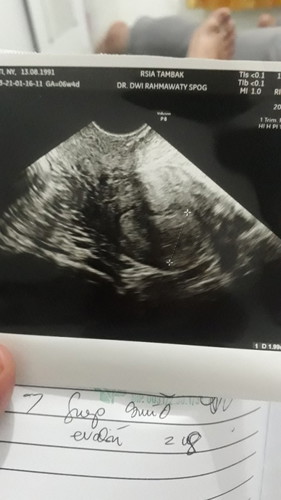

Share pengalaman bund, posisi bayi sungsang 30 week

Hallo bundaa.. Tadi habis kontrol usia kehamilan 30week, kondisi bayi sungsang dengan 1 lilitan dan berat 1,8. Dokter bilang bayi ukurannya besar, dan sulit untuk berubah posisi lagi jadi kemungkinan harus caesar untuk lahirannya. Tapi masih terus dipantau perkembangannya. Bunda2 disini ada yg punya pengalaman yg sama? Kalau kondisi sungsang dengan bayi besar usia 30week apa masih bisa muter lagi ya? Tapi apapun itu saya dan suami pasrahkan saja mau lahirnya gimana asal sehat bayi dan bunda nya. #seriusnanya #bantusharing #ingintahu #firstbaby #30week #sungsang